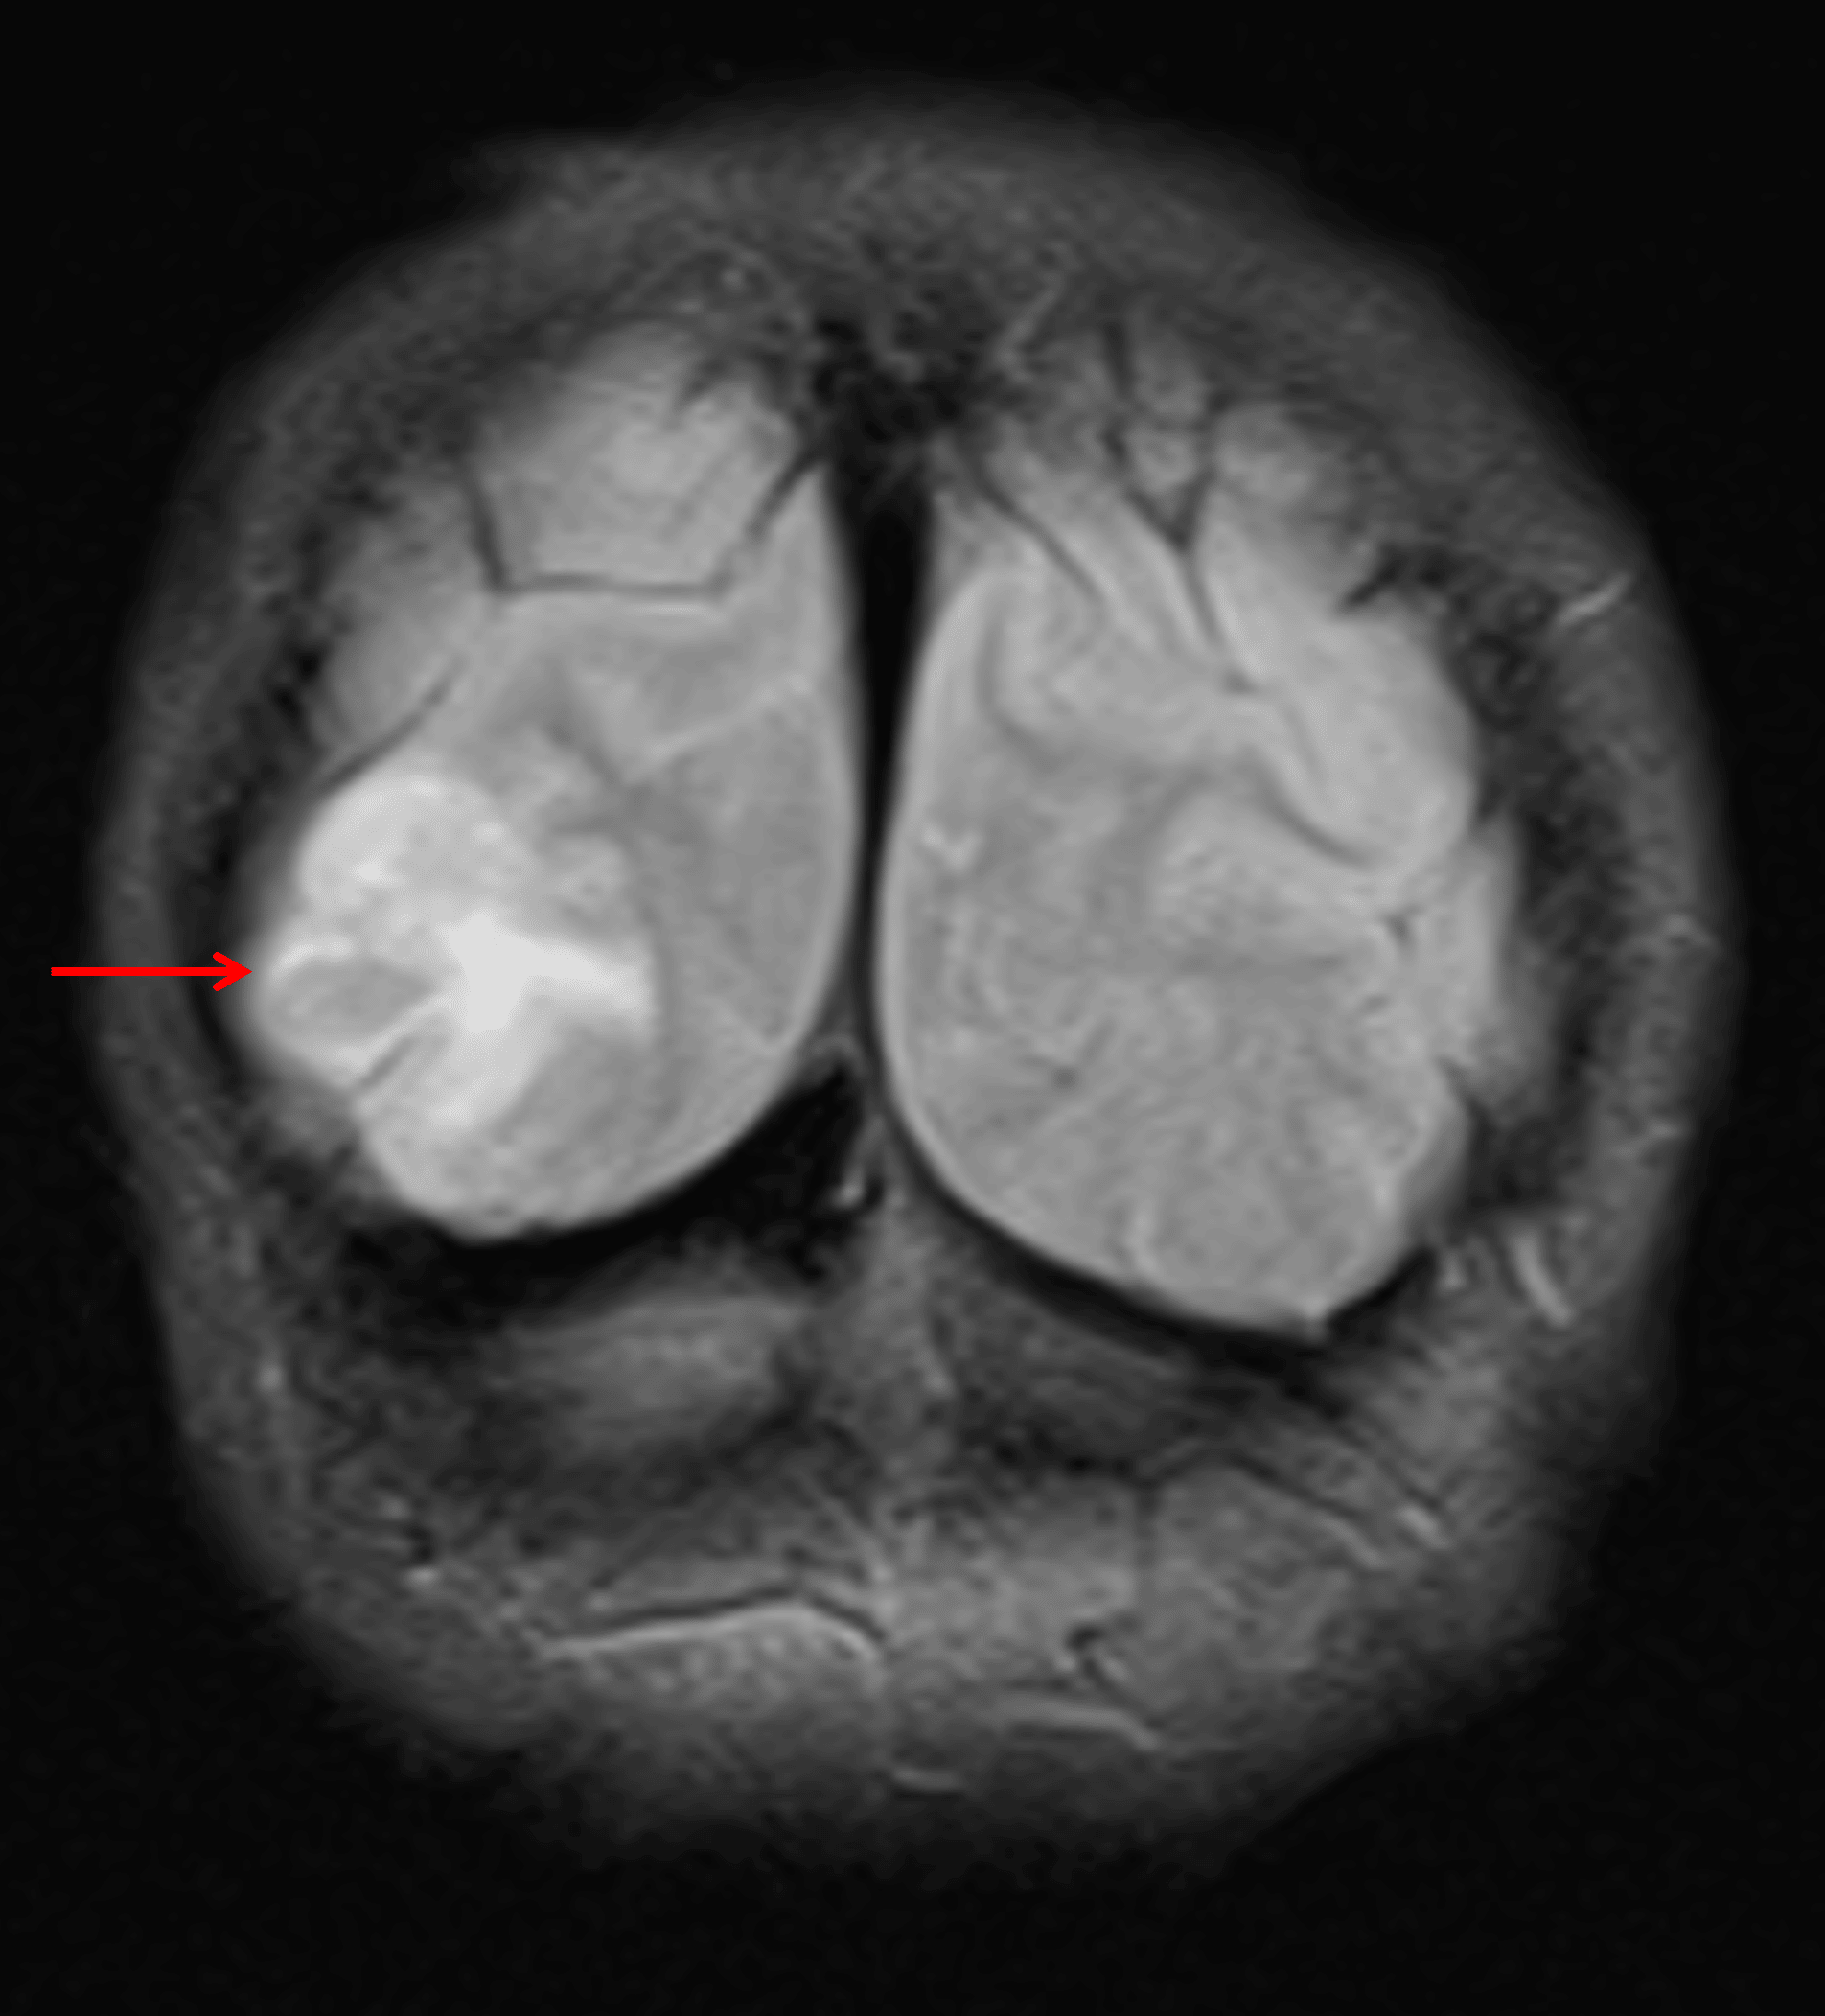

FLAIR hyperintense, expansile lesion in the right occipital lobe (red arrow).